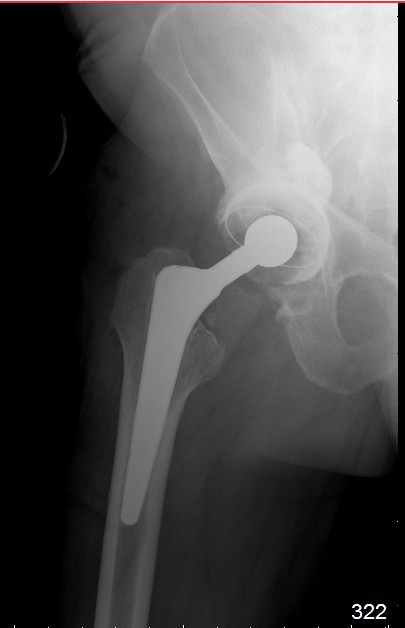

Пациент 60 лет, мужчина. Оперирован в 2007 году, поочередно оперированы два тазобедренных сустава с интервалом в 4 месяца. В 2008 году оперирован на сердце(аорто-коронарное шунтирование).Операция осложнилась инфицированием операционной раны в области грудины, лечился в гнойном отделении.

В конце 2008 года отметил боли в правой паховой области при опоре на правую ногу. На рентген снимках таза с тазобедренными суставами явных признаков нестабильности вертлужного компонента не обнаружено. В 2009 году нейрохирурги его "успешно" прооперировали на L\3-\4 связывая болевой синдром в правой паховой области с наличием грыжи указанного межпозвонкового диска. Состояние только ухудшилось, больной уже не мог долго сидеть, боль прогрессировала . Его в 2009 и 2010 годах смотрел ортопед, делались рентгенснимки, но почему то приходили к выводу что эндопротез справа стабилен. В марте 2011 года я впервые увидел его, через одну неделю после этого был прооперирован. На операции вертлужный компонент при упоре на него инструментом прокручивался во впадине и без труда был извлечен.

ниже снимок в 2008 году

далее снимок в 2009 году

далее снимок у меня на приеме